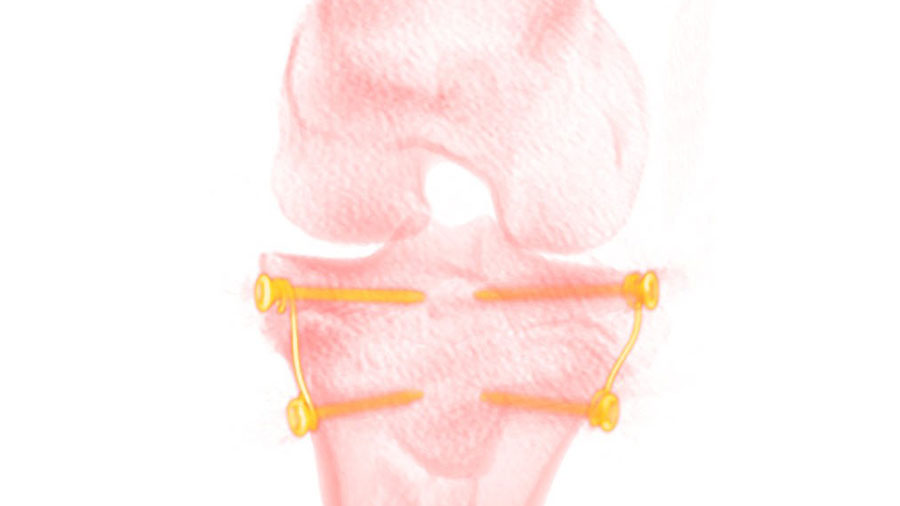

GoForce: Guided growth regulation revisited

Clinical problem

Limb deformities in children and adolescents are commonly corrected by the guiding growth technique whereby the deformity is equalized by inhibiting the growth with an implant. The treatment effect of currently utilized implant solutions is a function of growth. Hence, they require proper treatment planning and appear inefficient, particularly in correction of leg length discrepancies.

Proposed solution

A new constant force implant concept has been developed to realize controllable and efficient growth regulation. Treatment and outcomes are, thereby, rendered predictable. At the same time implant failures can be avoided.